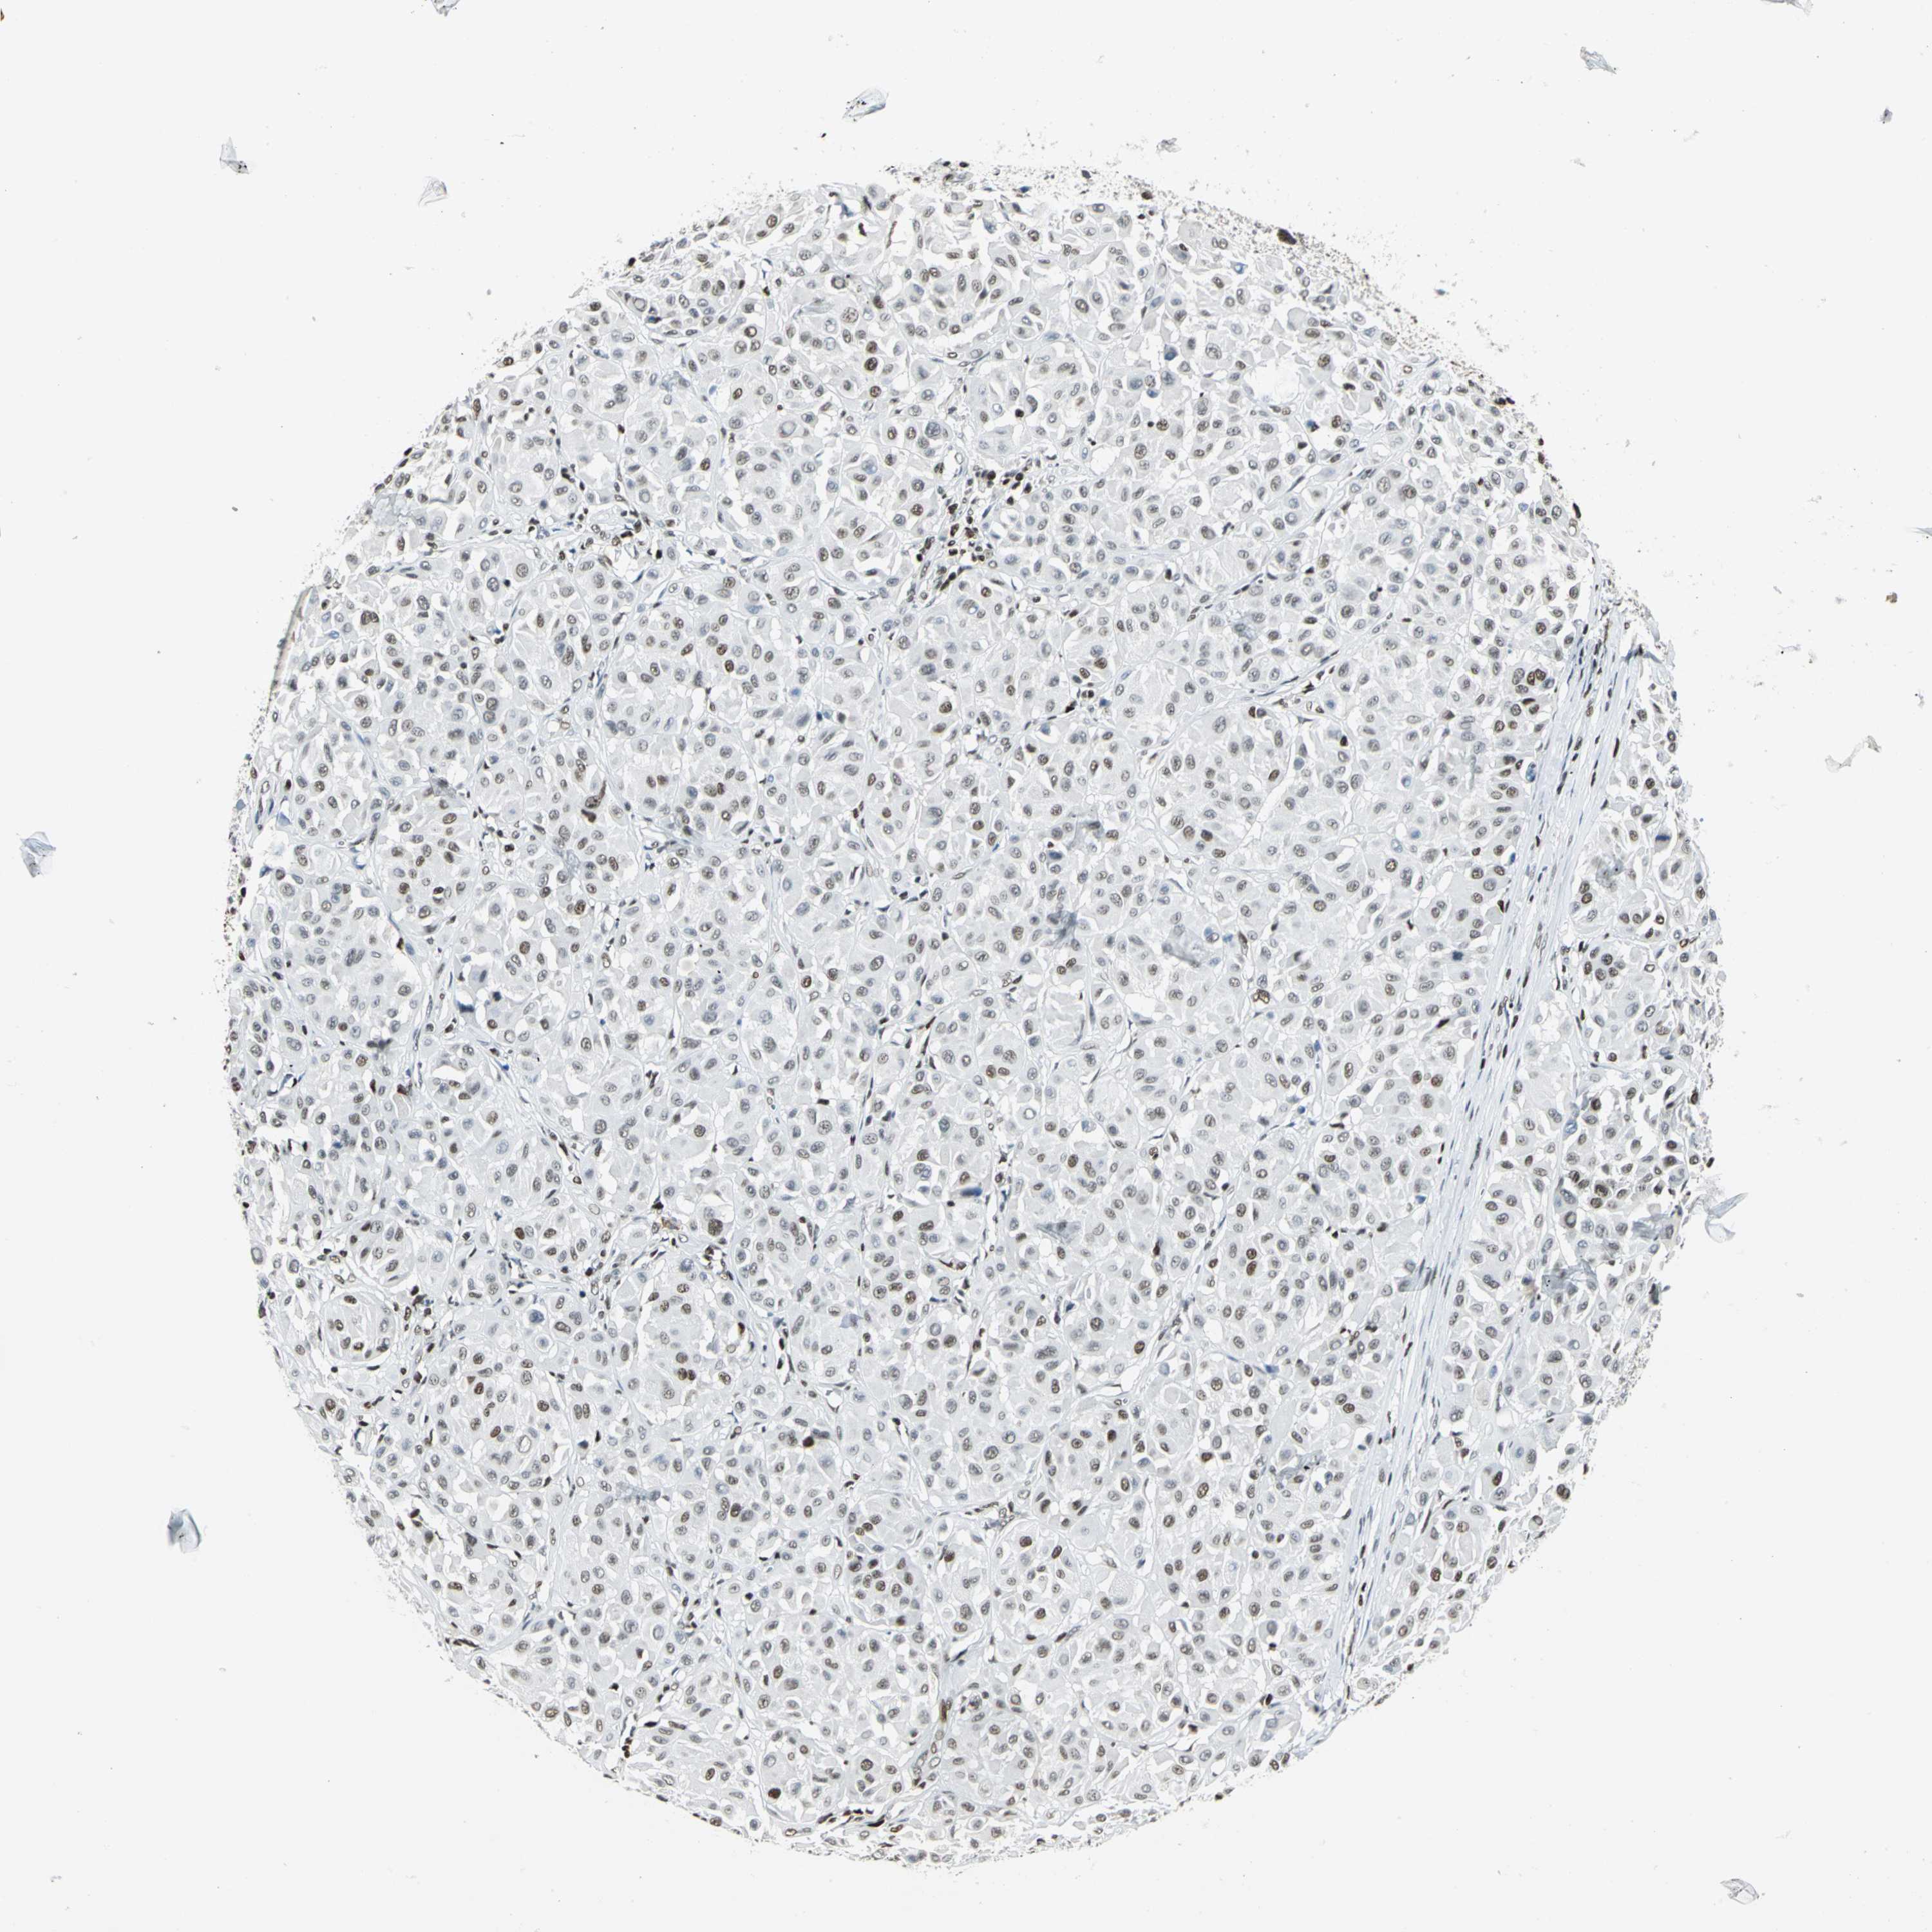

MELANOMA - Protein expressioni

A mouse-over function shows sample information and annotation data. Click on an image to view it in a full screen mode. Samples can be filtered based on level of antibody staining by selecting one or several of the following categories: high, medium, low and not detected. The assay and annotation is described here.

Note that samples used for immunohistochemistry by the Human Protein Atlas do not correspond to samples in the TCGA dataset.

Antibody stainingi

Antibody staining in the annotated cell types in the current human tissue is reported as not detected, low, medium, or high, based on conventional immunohistochemistry profiling in selected tissues. This score is based on the combination of the staining intensity and fraction of stained cells.

Each image is clickable and will lead to virtual microscopy that enables deeper exploration of all samples and also displays staining intensity scores, fraction scores and subcellular localization as well as patient and tissue information for each sample.

Antibody HPA004911

Staining

High

Medium

Low

Not detected

Intensity

Strong

Moderate

Weak

Negative

Quantity

>75%

75%-25%

<25%

None

Location

Nuclear

Cytoplasmic/membranous

Cytoplasmic/membranous,nuclear

Malignant melanoma, NOS

Malignant melanoma, Metastatic site